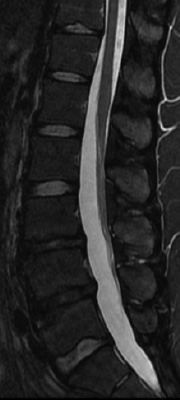

椎間板は、背骨(脊柱)を構成する椎骨と椎骨の間に存在し、背骨に加わる衝撃を緩和するクッションの役割を担っています。椎間板は中心部にゼリー状の髄核と呼ばれる柔らかい組織があり、その周囲の線維輪と呼ばれる丈夫な外層とで構成されています。髄核は子供ではゼリー状ですが、年齢とともにみずみずしさがなくなっていきます。この椎間板に強い圧力が加わったり、線維輪の弾力性が低下すると、亀裂が生じ、椎間板の内容物が押し出され突出します。これを椎間板ヘルニアと呼びます(図)。突出した椎間板が神経を圧迫すると下肢に痛みが生じることがあります。症状は、急性の激しい腰痛や下肢痛です。症状が進行すると下肢の力が入りにくくなり、つまづきやすいなどの運動障害が起こります。また、稀ではありますが、馬尾と呼ばれる腰椎部の神経が、ヘルニアにより強く圧迫されると、尿や排便の障害を生じることがあります。 痛みやしびれ感などの症状は、腰の前屈動作(前かがみ)や椅子に座った時に強くなることがあります。診察では、あお向けに寝て膝を伸ばした状態で片方ずつ足を持ち上げていく下肢伸展挙上テストで下肢に走る痛みが誘発されます。レントゲン検査では椎間板や神経の描出が困難なためMRIによる検査が必要です(図)。

椎間板は脊柱(せぼね)の構成成分の1つであり、椎骨と椎骨の間に存在し、脊柱に動きをもたせ、クッションとしての役割も担っています。椎間板は中央の髄核(ゼリー状の柔らかい組織)とそれを取り囲む丈夫なコラーゲン線維からなる線維輪で構成されています。椎間板に常に負担がかかっており加齢やストレスなどで髄核の水分が減少して変性という現象(すなわち老化)が起こってきます。こうした老化現象によって椎間板の支持性やクッションとしての機能が低下すると、周りの神経を刺激したり、靭帯、関節や筋肉に負担がかかり、腰痛の原因になることがあります。このように椎間板の変性による腰痛が生じた状態を腰部椎間板症と呼びます。症状は急性、慢性の腰痛で体動時(特に前屈位)に痛みが強くなることが多く、下肢症状や膀胱直腸症状は伴うことはまれです。腰椎椎間板症は、診察だけでは診断が難しい場合もあり、レントゲンでも大きな異常が認められない事も少なくないため、MRIという画像検査が必要になる場合もあります(図)。

脊髄腫瘍とは脳からの信号を手や足に伝達する神経の束である脊髄やその枝にできる腫瘍です。脊髄腫瘍は脳腫瘍より数が少なく、一年間に10万人当たり1~2人程度の発生頻度といわれています。腫瘍の発生する部位によって硬膜外腫瘍、硬膜内髄外腫瘍、髄内腫瘍の3つに分類されます(図1)。最も頻度の高い硬膜内髄外腫瘍は脊髄を外から圧迫する形で発育し、運動麻痺や感覚障害、膀胱直腸障害といった症状を呈します。発生する腫瘍の種類としては神経鞘腫(図2)や髄膜腫といった良性のものが多く、ゆっくりと成長するため、腫瘍がかなり大きくなるまで症状が出ない場合もあります。髄内腫瘍は脊髄の中で腫瘍が成長し、正常脊髄を内側から圧迫します。やはり運動麻痺や感覚障害、膀胱直腸障害といった症状を呈します。発生する腫瘍は上衣腫(じょういしゅ)、星細胞腫(せいさいぼうしゅ)、血管芽細胞腫(けっかんがさいぼうしゅ)などがみられます。これらの腫瘍も確実に発育するため手術治療(腫瘍摘出術)が原則となります。しかし、正常脊髄と腫瘍の区別が困難で全摘出が出来ないこともあり、機能的および生命予後は腫瘍の種類に左右されます。

図2:硬膜内髄外腫瘍(神経鞘腫)のMRI側面像 (T2強調像:左図)とMRI横断像(T1造影:右図)。

腫瘍(黄矢印)により脊髄(白矢印)が高度に圧迫されている。